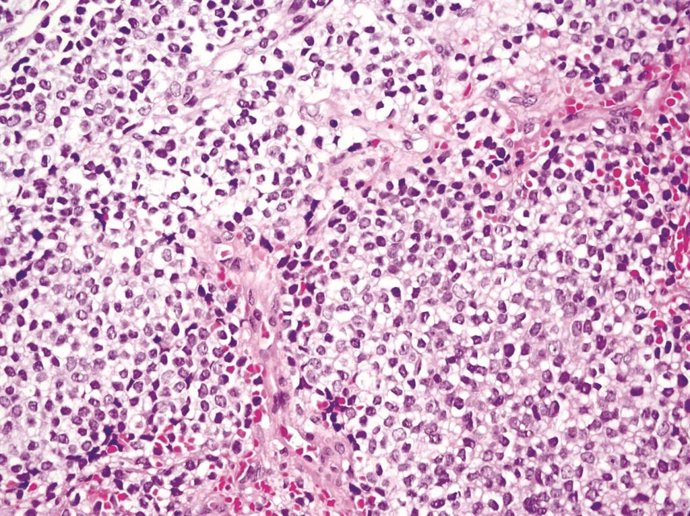

Sarcoma de Ewing.

Sarcoma de Ewing. - UNIVERSIDAD DE SEVILLA

Un equipo del Instituto de Biomedicina de Sevilla (IBiS) ha identificado un nuevo mecanismo molecular que podría explicar la elevada sensibilidad del sarcoma de Ewing --un tumor óseo agresivo que afecta principalmente a niños y adolescentes-- a determinados fármacos quimioterápicos, como el irinotecán, según un estudio publicado en la revista Oncogene. Los investigadores han señalado que estos hallazgos podrían abrir la puerta a estrategias "más personalizadas y eficaces" para el tratamiento de este tipo de cáncer.

La entidad ha explicado que el sarcoma de Ewing está caracterizado por una alteración genética muy específica: la fusión de los genes Ewsr1 y FLI1, que da lugar a una proteína quimérica oncogénica denominada EWS::FLI1. Esta fusión, además de iniciar y sostener el crecimiento tumoral, altera procesos celulares esenciales.